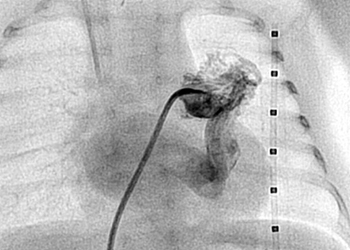

نجح فريق طبي بقيادة الدكتور عمر التميمي استشاري القسطرة التداخلية بمدينة الملك عبدالعزيز الطبية بإجراء عملية قسطرة نادرة لطفل سعودي خديج عبارة عن اتصال بين الشريان الرئوي والوريد الرئوي.

وقد كان الطفل يعاني من انخفاض مستوى الاكسجين في الدم ويعتمد بشكل كامل على جهاز التنفس الصناعي منذ ولادته، حيث اجريت له عملية قسطرة تداخلية في مدينة الملك عبدالعزيز الطبية بالحرس الوطني تم من خلالها تحديد الشرايين في الرئة اليسرى ومن ثم اغلاق 80% من الشرايين غير الطبيعية في المرحلة الاولى بواسطة ثلاث سدادات وعائية.

وبعد العملية تحسن تركيز الاكسجين في الدم بفضل الله بنسبة تراوحت ما بين 80-90% وتم فصل جهاز التنفس بنجاح دون حدوث أي مضاعفات ويتوقع خروج الطفل الى منزله في الايام القريبة المقبلة.

وتعتبر هذه الحالة نادرة الحدوث للأطفال وبالأخص حديثي الولادة وتحتاج لتدخل جراحي أو قسطرة تداخلية، وقد قرر الفريق الطبي اجراء المرحلة الثانية من العملية عندما يصل الطفل الى 6 او 8 اشهر تقريبا.